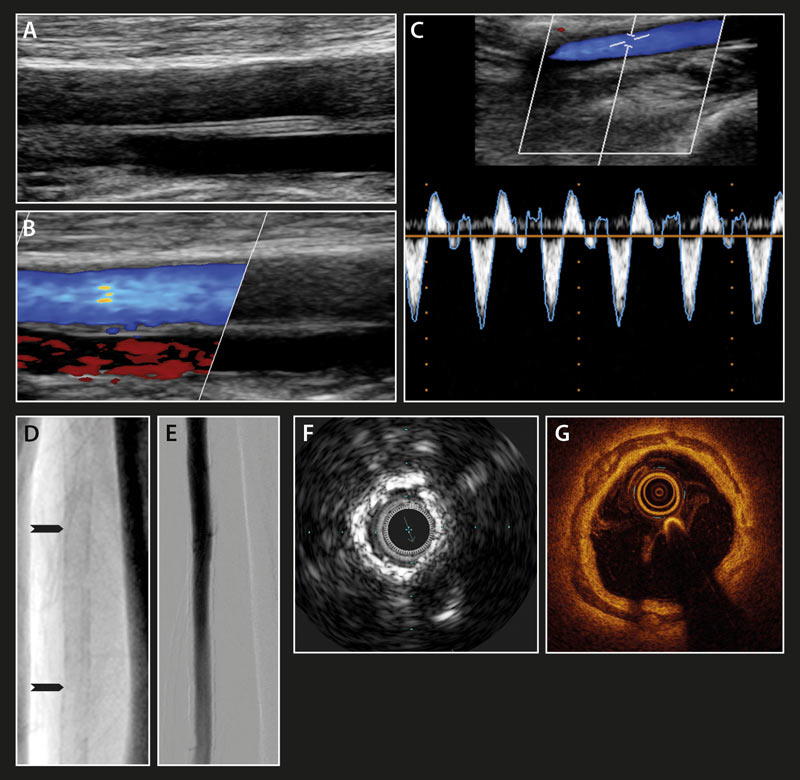

Im Gefäßultraschall sind die, für die Mediasklerose typischen, linearen Streifen mit verstärkter Echogenität entlang der longitudinal abgebildeten Schallkopf-nahen Gefäßwand nachweisbar. Beim Fehlen einer begleitenden Arteriosklerose sind die endothelialen Grenzflächen glatt. Im Farbdoppler zeigt sich in diesen Fällen ein homogenes Blutfluss-Signal. Mittels intravaskulären Ultraschalls und der optischen Kohärenztomographie werden die medialen Verkalkungen als echogene, bzw. als signalarme bogige Streifen erkennbar. In der Abbildung 4 sind einige typische Beispiele der bildgebenden Diagnostik bei Patienten mit einer Mediasklerose zusammengefasst. Beim Vorliegen einer Mediasklerose sollten laborchemische Bestimmungen des Kohlenhydrat- und Fettstoffwechsels, der Nierenwerte sowie der Plasmaspiegel des Parathormons und des Vitamin D

Abbildung 4: Mediaverkalkungen im Spiegel der bildgebenden Verfahren. Dargestellt ist Mediasklerose (roter Pfeil) der Arteria femoris superficialis im Gefäßultraschall: B-Bild (A), Farbduplex (B) und PW-Duplex (C), im Röntgenbild: natives Röntgenbild (D), Digitale Subtraktionsangiographie (DAS) (E). intravaskulärer Ultraschall (F) und optische Kohärenztomographie (G). (modifiziert und reproduziert mit freundlicher Genehmigung des Deutschen Ärzteblattes).